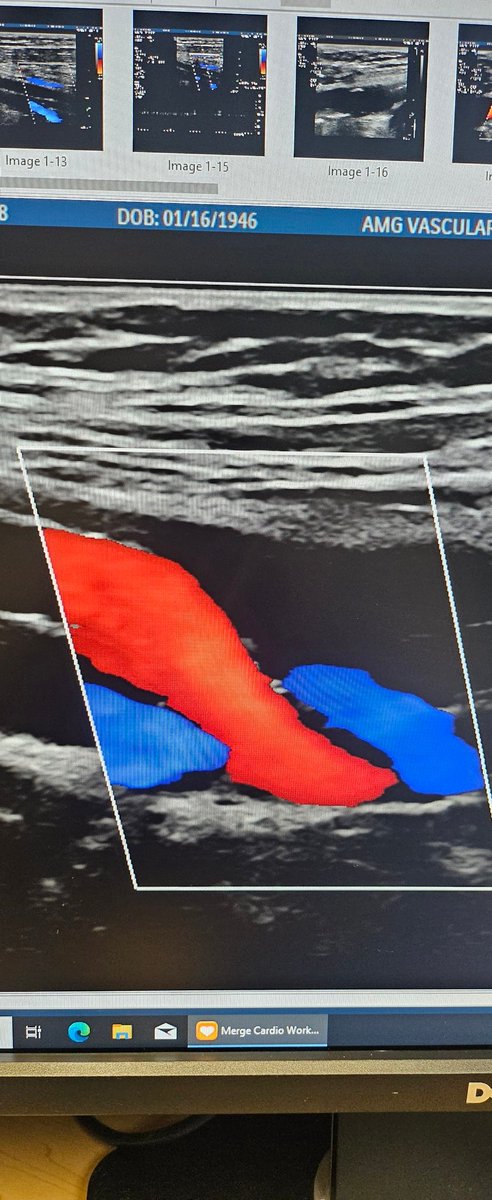

First glimpse of #PTAB w #Detour @endologix 3 week surveillance arterial duplex @ShawnPenn33 @DeanFerreraDO @MarcoShaker @kymbee @tlevin